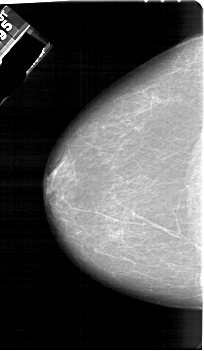

A_1161_1.LEFT_MLO

A_1161_1.RIGHT_MLO

A_1161_1.LEFT_CC

A_1161_1.RIGHT_CC

LEFT_CC LINES 6301 PIXELS_PER_LINE 3661 BITS_PER_PIXEL 12 RESOLUTION 43.5 NON_OVERLAY

LEFT_MLO LINES 6451 PIXELS_PER_LINE 3631 BITS_PER_PIXEL 12 RESOLUTION 43.5 NON_OVERLAY

RIGHT_CC LINES 6256 PIXELS_PER_LINE 3661 BITS_PER_PIXEL 12 RESOLUTION 43.5 NON_OVERLAY

RIGHT_MLO LINES 6181 PIXELS_PER_LINE 3781 BITS_PER_PIXEL 12 RESOLUTION 43.5 OVERLAY

FILE: A_1161_1.RIGHT_MLO.OVERLAY

TOTAL_ABNORMALITIES 1

ABNORMALITY 1

LESION_TYPE MASS SHAPE IRREGULAR MARGINS ILL_DEFINED

ASSESSMENT 4

SUBTLETY 1

PATHOLOGY MALIGNANT

TOTAL_OUTLINES 1